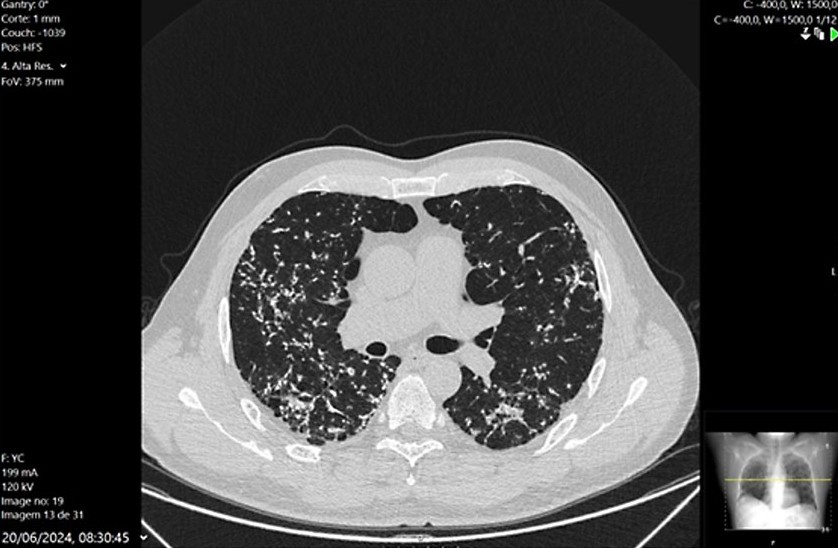

• Dendriform Pulmonary Ossification in a Patient with Fibrotic Interstitial Lung Disease

Nuno Pardal, Patrícia Tinoco Araújo, Luís Pontes dos Santos

188-190

DOI: https://doi.org/10.60591/crspmi.469